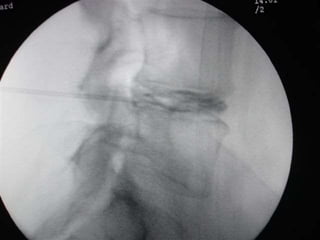

 Intervertebral disc of interest was squared in antero-positerior

projection. Scotty Dog projection was attained in oblique view.

 Percutaneous Needle was placed under local anesthesia under C-arm

guidance with Utmost care to avoid nerve roots contact and whenever patient

complain of pain radiating to legs the direction of needle was changed.

 Needle advancement was performed under fluoroscopic control with AP

and Lateral views.

 Annulus fibrosus puncture can be both felt as well as seen under

fluoroscopy.

 Working distance of disc was determined and needle guard was placed

accordingly.

 Stylet was removed and Stryker decompressor was placed in a needle

and properly locked.

 The decompressor was switched on and needle and decompressor

were moved as a single unit over a distance of one centimeter or as

directed by C-arm picture and about 1-1.5ml of gelatinous nucleus

pulposus was removed.

.  Material andmethods:  Percutaneous ablating techniques of intervertebral disc are performed under fluoroscopy guidance with patients in prone position for lumbar discectomy.  Pre-procedural antibiotic (Amoxiclav 1.2gm) was given 45 minutes prior to the procedure.  Under all aseptic precautions, standard ASA monitored attached , iv line secured with 20 gauge iv cannula and iv fluid started @ 100ml/hr  Conscious sedation was attained with intravenous midazolam 1mg and IV fentanyl 1mcg/ Kg and repeated if required.  Intervertebral disc of interest was squared in antero-positerior projection. Scotty Dog projection was attained in oblique view.  Percutaneous Needle was placed under local anesthesia under C-arm guidance with Utmost care to avoid nerve roots contact and whenever patient complain of pain radiating to legs the direction of needle was changed.  Needle advancement was performed under fluoroscopic control with AP and Lateral views.

 Annulus fibrosuspuncture can be both felt as well as seen under fluoroscopy.  Working distance of disc was determined and needle guard was placed accordingly.  Stylet was removed and Stryker decompressor was placed in a needle and properly locked.  The decompressor was switched on and needle and decompressor were moved as a single unit over a distance of one centimeter or as directed by C-arm picture and about 1-1.5ml of gelatinous nucleus pulposus was removed.  After completion of procedure 1ml of injection Acuclav was given in the disc space.  Assembly was removed and aseptic dressing was applied.  The patient was asked to move his lower limb to check any injury to nerves by comparing with other side.  Patient kept in recovery for 3 hrs and sent home if fit with clear instructions to accompanying person.